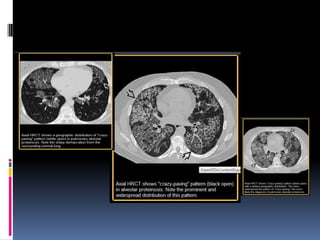

EMPEDRADO PATRON CRAZY

PAVING

 CT-scans. Este patrón aparece como septos

interlobulillares engrosados ​y intralobular líneas

superpuestas en una fondo de vidrio deslustrado.

semejante a una forma irregular pavimentación

piedras.

 El patrón de empedrado es a menudo bien

delimitado.

 También se informó originalmente en pacientes

con proteinosis alveolar y también se encuentra

en enfermedades que afectan tanto al intersticio

y los compartimientos del espacio aéreo, tales

como neumonía lipoide .

EMPEDRADO PATRON CRAZY PAVING CT-scans. Este patrón aparece como septos interlobulillares engrosados ​y intralobular líneas superpuestas en una fondo de vidrio deslustrado. semejante a una forma irregular pavimentación piedras.  El patrón de empedrado es a menudo bien delimitado.  También se informó originalmente en pacientes con proteinosis alveolar y también se encuentra en enfermedades que afectan tanto al intersticio y los compartimientos del espacio aéreo, tales como neumonía lipoide .